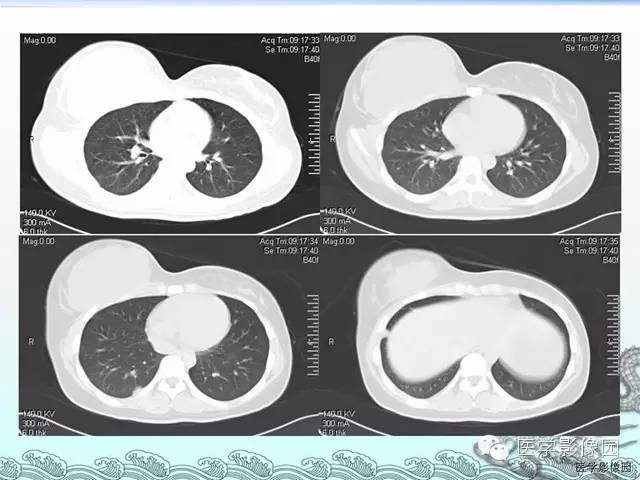

胸壁结核1例影像表现

【病例】胸壁结核1例影像表现